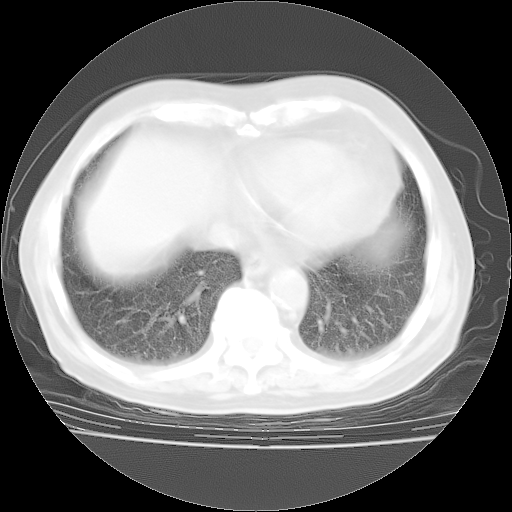

4月28日肺部CT——再次出现类似去年5月9日——透光度降低,“间质性”改变。

4月28日肺部CT——再次出现类似去年5月9日——磨玻璃样、间有“粟粒样”改变。

4月28日肺部CT